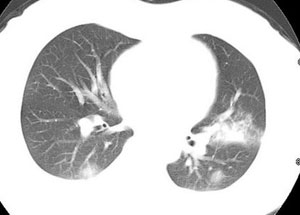

女性,30岁。

病史为胸痛20多天,无畏寒发热,无消瘦,无咳嗽咳痰。总之症状很逍遥。

临床以胸痛待查收住入院。

双肺野可见散在大小不等结节及肿块影,内密度不均匀,边缘部分清,部分欠清,纵隔未见明显肿大淋巴结.右侧胸腔少理积液.结合临床,考虑韦格肉芽肿可能吧,巨淋巴增生,结节病,特殊感染都要考虑.转移瘤临床不象.

本病例特点如下:

1.青年女性,以胸痛20多天就诊,无呼吸道及感染临床症状体征,无原发肿瘤病史;

2.肺ct表现为两肺多发大小不等结节影,大结节位于肺尖部,小结节多位于肺外带胸膜下,大结节内可见支气管充气征,周围可见月晕征(指在结节状或肉芽肿样病灶周围呈环形磨玻璃影),右肺门及腔静脉后可见小淋巴结,右侧胸腔内少量液体。

两肺散在分布大小不等的肿块及结节影,边缘毛糙,有分叶、毛刺,病灶密度不均匀,可见支气管充气相与空泡征。病变大多位于胸膜下,可见胸膜凹陷及胸腔积液。气管腔静脉间可见小结节影。